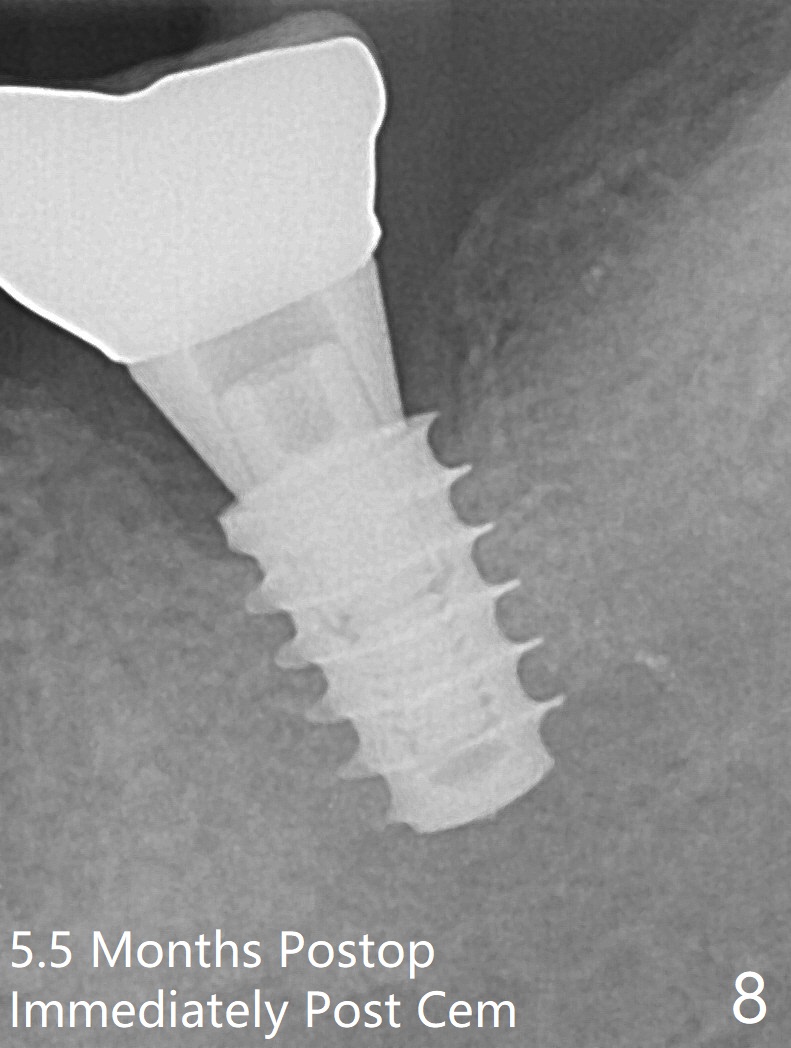

Six months post socket preservation at #18 (with moderate atrophy, Fig.1), a simplified surgical guide (Fig.2 with metal sleeve of 5 mm height and 2.93 mm diameter) determines initial osteotomy with 3.3 mm Magic Drill (MD), followed by 4.8 mm MD for 9 mm (gingival level) free hand. Since a 5x7 mm IBS implant is placed incompletely and in low stability (Fig.3 (in the graft bone)), a 4.3 mm MD is used for ~1 mm deeper. The implant is reseated to more satisfactory level (Fig.4: ~ 1 mm from the upper border of the Inferior Alveolar Canal (red dashed line)). The fearful patient is extremely pleased with quickness of the procedure as compared to that at #30 free hand. The wound heals normally 2 weeks postop. When she finishes the follow up appointment, she voluntarily talks to another patient who is hesitant about implant treatment. Impression is taken 5 months postop (Fig.5,6). There is no gap between the crown and abutment using abutcoping technique (Fig.7,8). The crown at #18 looks low probably related to long termed edentulism (Fig.9). The access hole is lingual (Fig.9), because the implant was placed lingual (Fig.10) due to use of a partial guide (Fig.11).